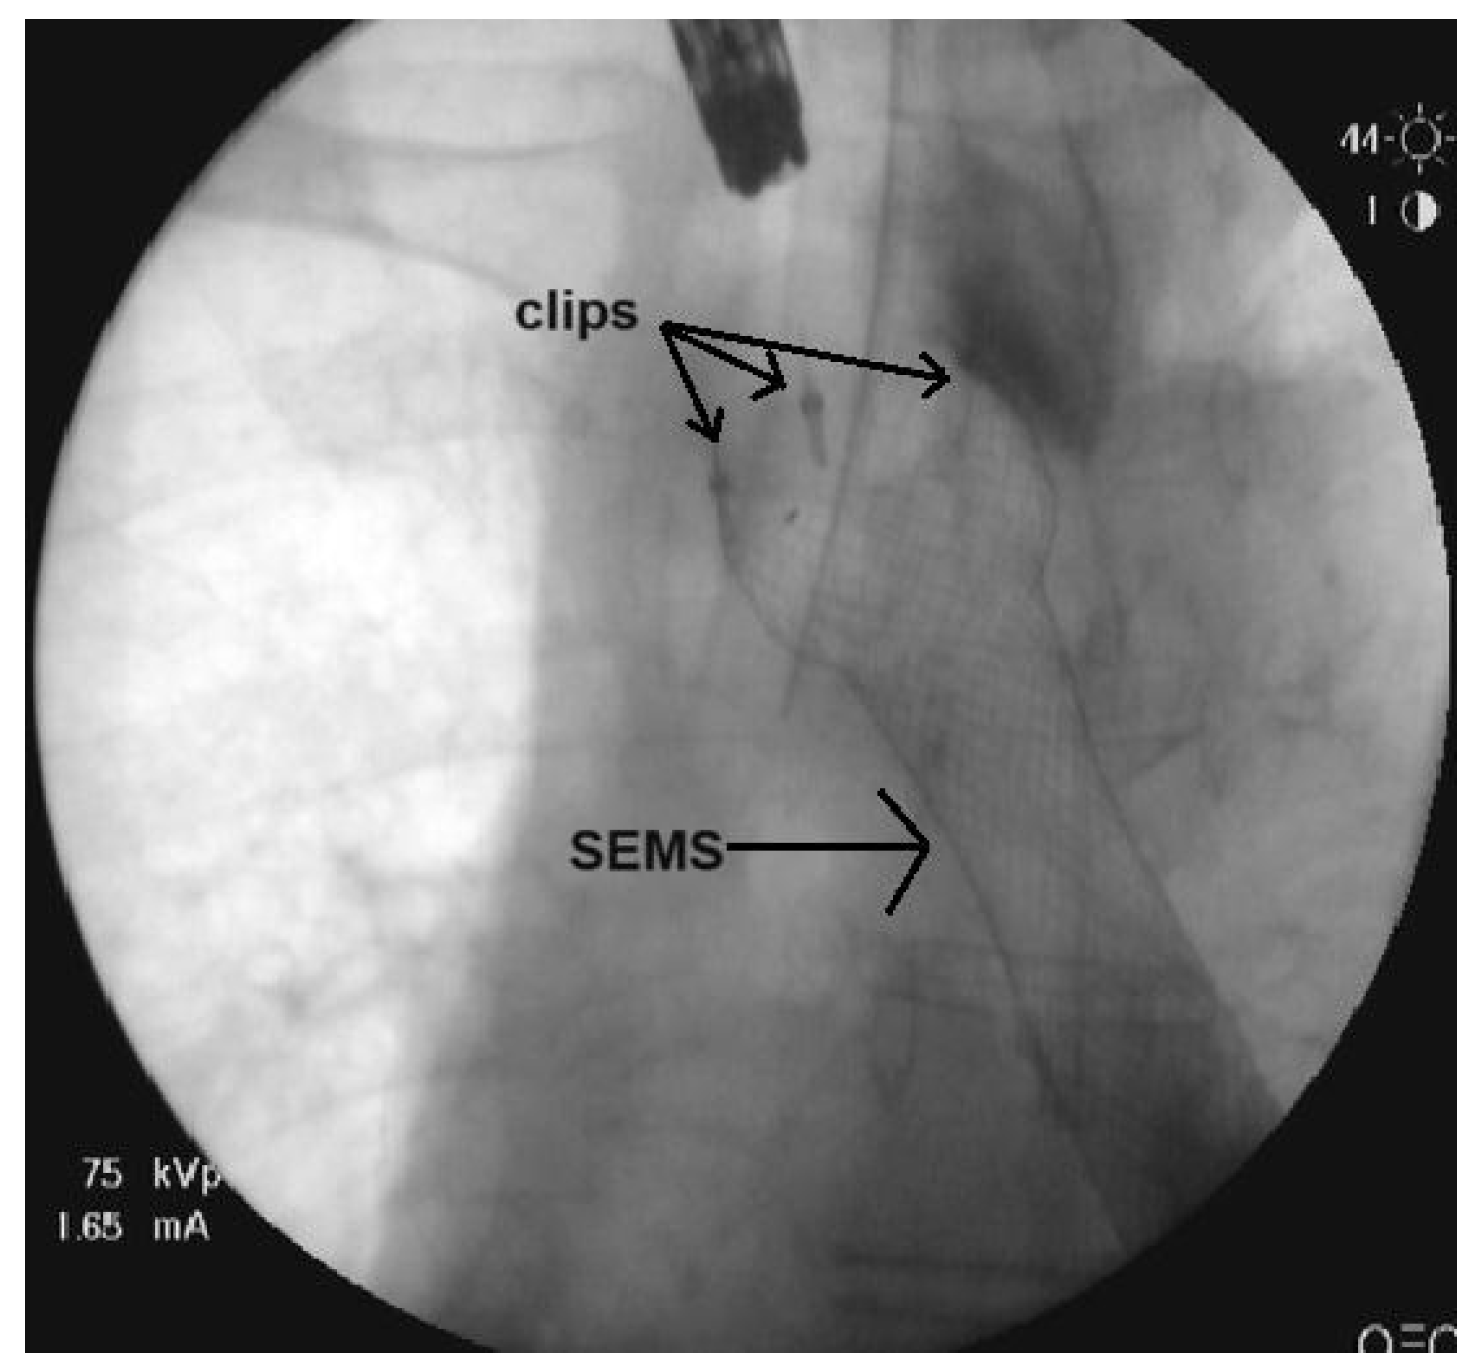

Prevention of Migration of Esophageal Self-Expandable Metallic Stents Using Endoscopic Clips

2. Materials and Methods

3. Results